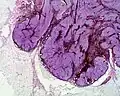

A blue nevus is a type of coloured mole, typically a single well-defined blue-black bump.[1][2]

The blue colour is caused by the pigment being deep in the skin.[4]

• A cellular blue nevus is a cutaneous condition characterized by large, firm, blue or blue-black nodules.[7]:701